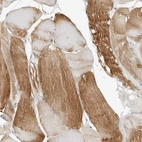

Immunohistochemical staining of human skeletal muscle shows strong cytoplasmic positivity in myocytes.